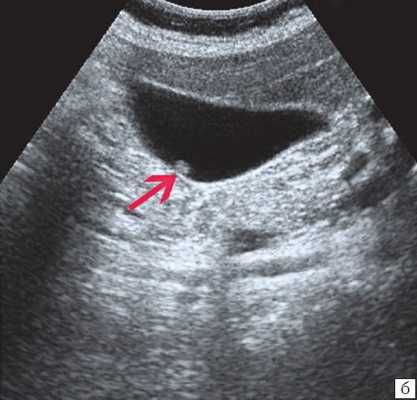

Ультрасонография является эффективным средством выявления полиповидной формы холестероза 7. Традиционной считается следующая сонографическая характеристика холестериновых полипов: неподвижные гиперэхогенные структуры, которые не дают акустической тени и прикрепляются к стенке желчного пузыря. Контуры таких образований, как правило, ровные, а размеры таких образований различны, чаще не превышают 10 мм (рис. 2).

a) Одиночный полип в желчном пузыре (гиперэхогенное пристеночное неподвижное образование, с ровными контурами, без акустической тени).

б) Одиночный полип в желчном пузыре.

в) Полиповидно-сетчатая форма холестероза, полипы размерами до 5 мм, повышенной эхогенности.

г) Одиночный полип в желчном пузыре.

Однако, по некоторым данным, размеры холестериновых полипов могут быть более 20 мм. Кроме того, полипы больших размеров (в 7% от общего числа) могут иметь пониженную эхогенность и фестончатый контур.

Мелкие холестериновые включения, образующие диффузную сеточку в толще подслизистого слоя размерами 1-2 мм, выглядят как локальное утолщение или уплотнение стенки желчного пузыря и в некоторых случаях (см. рис. 2) вызывают реверберацию (эхографический симптом "хвост кометы").